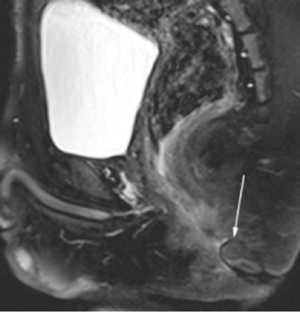

Perianal complications of Crohn disease are a common occurrence in children and can result in significant morbidity when not accurately characterized prior to surgical intervention. MRI is an excellent imaging modality for the evaluation of perianal inflammatory bowel disease – allowing characterization and detailed description of perianal fistulas. MRI has many advantages over other imaging modalities for the pediatric patient. Radiologists will benefit from a sophisticated understanding of perianal anatomy, the classification of perianal fistulas, the advantages MRI offers in characterization of perianal fistulas as well as the common and incidental findings that are important in the MRI evaluation of perianal inflammatory bowel disease in children. Perianal fistulas are found at a high rate in pediatric referrals and are more commonly found in male patients.

Fig. 3